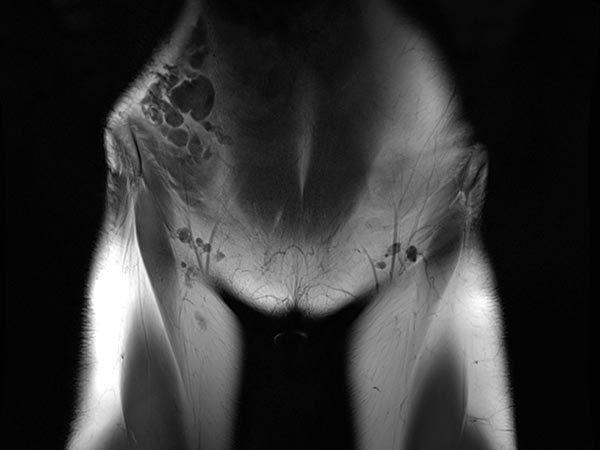

Koronare, T2-gewichtete, fettunterdrückte MRT des Unterbauchs auf Höhe der Leisten. Unauffällige Leistenlymphknoten. Die lymphatische Malformation der Bauchwand stellt sich in großen, dysplastischen, ballonartigen, gekammerten Zysten dar, die stark hyperintens (weiß) sind.

Makrozystische lymphatische Malformationen (LM), die direkt an der Haut liegen, können durch den hohen lokalen Lymphdruck zu einem Durchtritt von Lymphflüssigkeit durch die Haut über kleine Hautbläschen (Lymphvesikel) führen. Diese Areale werden Lymphangioma circumscriptum genannt. Durch eine Sklerosierungstherapie (hier mit Picibanil = OK-432) werden die Lymphkanäle über eine starke lokale Entzündung verschlossen und die Haut abgedichtet. Günstig in diesem Fall die größeren Anteile der lymphatischen Malformation, die miteinander kommunizieren (nach Injektion von KM über die Punktionsnadel sichtbar). Daher sind nur wenige Punktionen notwendig um die gesamte lymphatische Malformation zu sklerosieren. Dieses minimalinvasive Verfahren ist meist auf Dauer schonender als offen operative Maßnahmen, da einzelne, auch kleine Kammern in den oft fuchsbauartig verzweigten LM mit dem flüssigen Sklerosierungsmittel leicht erreicht werden können.